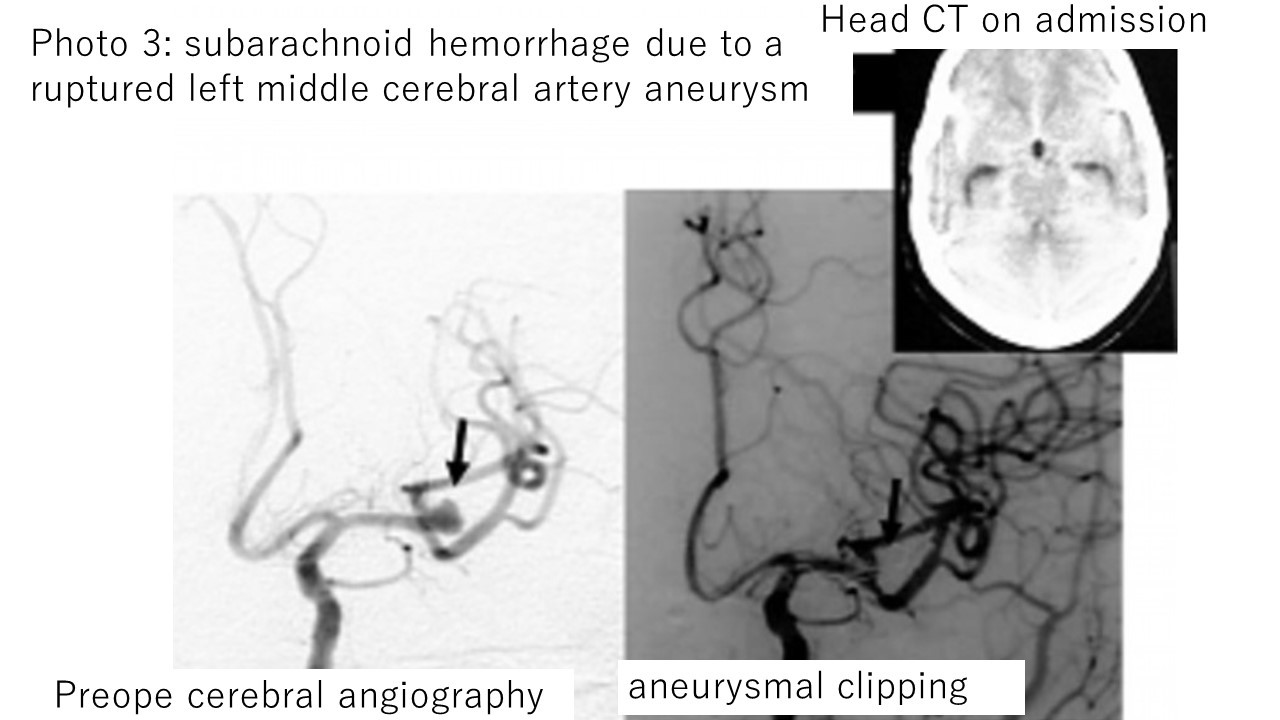

Photo 3: Clipping surgery for subarachnoid hemorrhage (left middle cerebral aneurysm rupture).

The image on the left is a cerebral angiography before surgery, and the image on the right is a cerebral angiography after surgery.

If a cerebral aneurysm reruptures, the mortality rate rises sharply, so an emergency cerebral angiography test is performed to accurately determine the location of the aneurysm, and as a general rule, within 24 hours or less, clipping to stop rebleeding within 48 hours. Surgery (or endovascular coil embolization) is performed (however, if the patient's condition is too bad, surgery itself may not be possible).

After surgery, we aim to return to society by appropriately treating cerebral vasospasm and hydrocephalus.

Photographs 1 to 4 explain the clipping surgery for aneurysms in four different sites that I actually performed for subarachnoid hemorrhage (all of these cases were fortunately free from symptoms and left the hospital on their own).